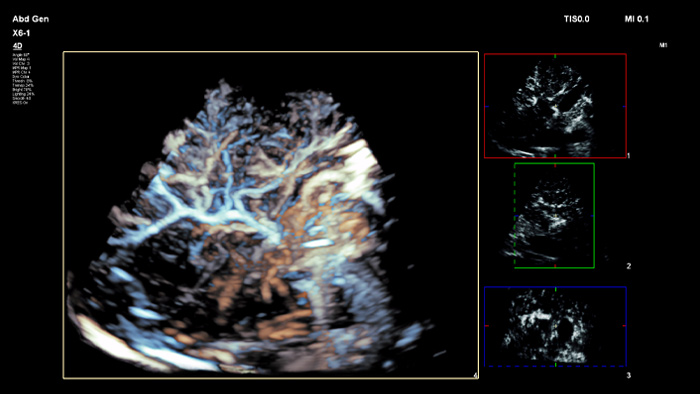

Les agents de contraste échographiques peuvent transformer le rôle de l'échographie dans l'évaluation du foie en permettant d'étudier les schémas de rehaussement des lésions hépatiques suspectes en temps réel pour un diagnostic plus rapide et plus sûr.

Vous avez besoin d'une excellente résolution des détails, d'une sensibilité Doppler et de performances d'échographie améliorée par contraste (CEUS) ?

La technologie cristalline PureWave est faite pour vous ! Elle représente la plus grande avancée dans le domaine des sondes piézoélectriques depuis 40 ans. Elle est 85 % plus efficace que les matériaux piézoélectriques classiques, ce qui se traduit par des performances exceptionnelles pour toutes les morphologies de patients.